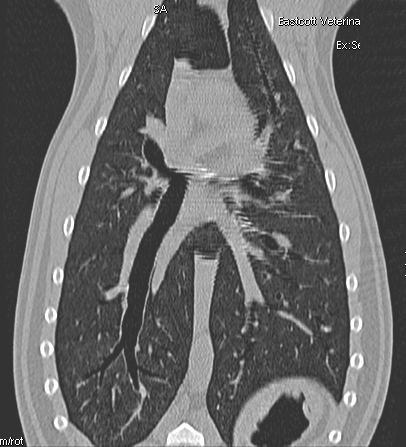

Fig 3

CT image at 2-week re examination